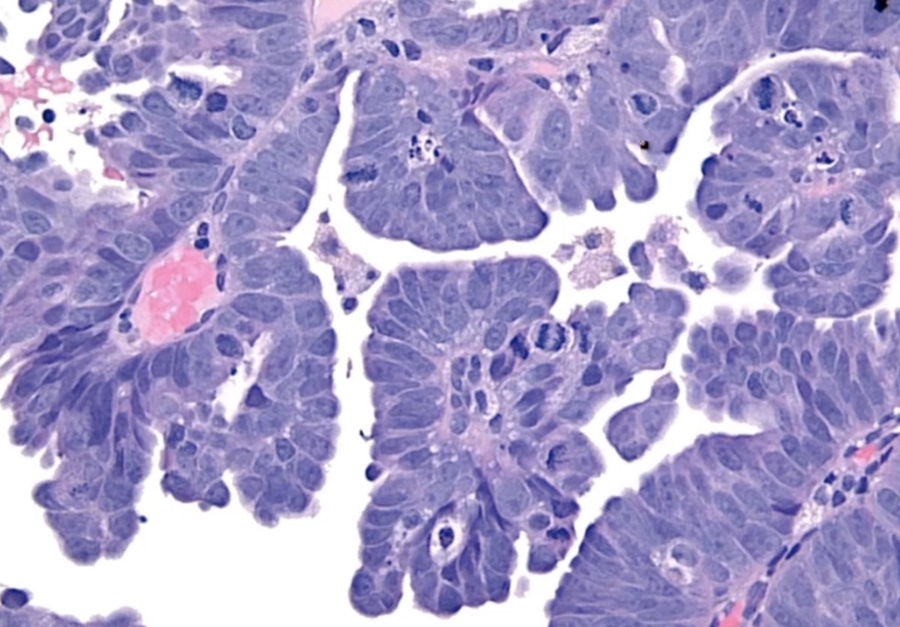

High grade dysplasia (carcinoma in situ) in the uterine cervix. The abnormal epithelium is extending into a mucus gland to the left of centre. This disease can progress to invasive cancer (squamous cell carcinoma) of the cervix:

CIN III

Development of dysplasia and carcinoma of the cervix. Repeated human papillomavirus (HPV) infections convert normal epithelium (left) into increasingly severe dysplasia until malignant epithelium breaks through the basement membrane to become invasive cancer‚ capable of metastasis by invasion of blood vessels and lymphatics.

_CIN I to III can regress. CIS cannot regress and will proceed to invasive squamous cell carcinoma once it breaks through basement membrane.

_Carcinoma in situ is characterized by atypical changes extending through the entire thickness of the epithelium.

As it has not yet invaded the basement membrane, it is considered a precancerous lesion.